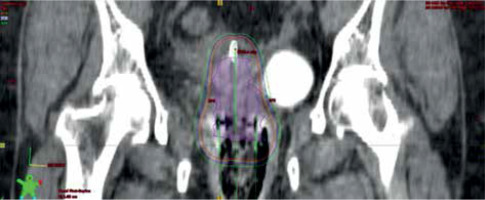

Fig. 2

Coronal section of CT scan of ICBT application with isodose distribution. Represented isodose levels are 100% dose (orange), 90% (blue), and 80% (green)